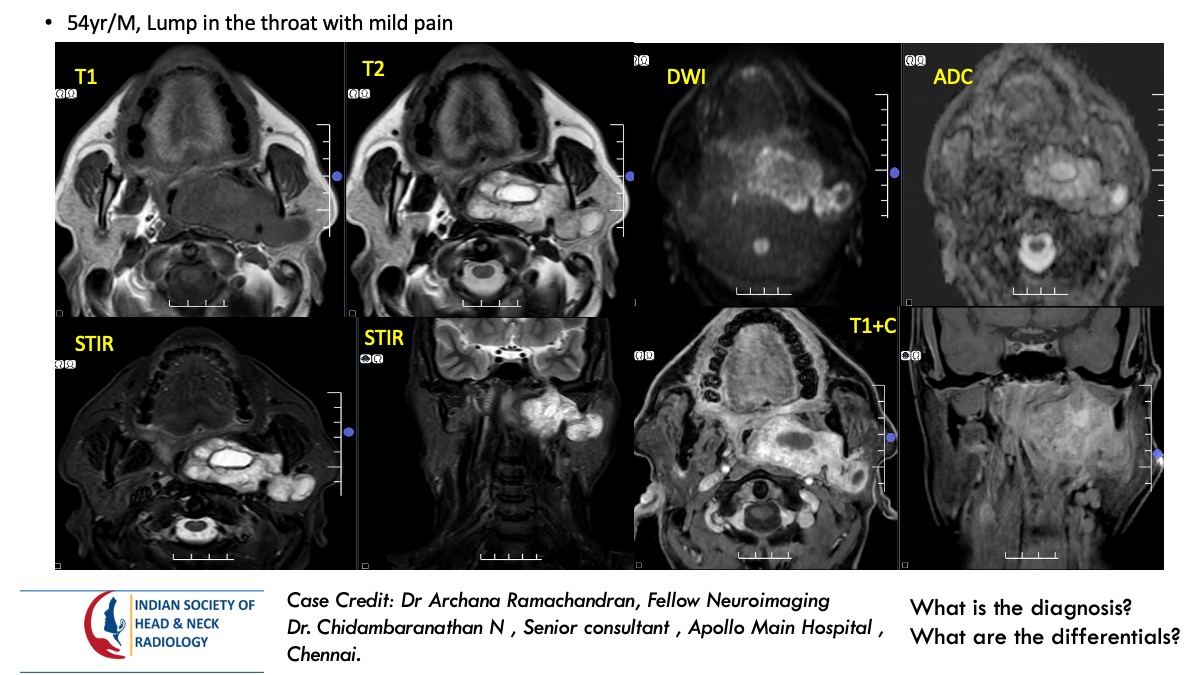

Please find the answer